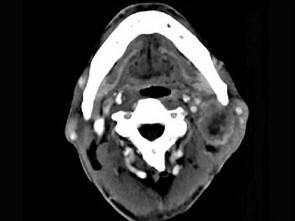

问题 65岁男性,吸烟史30余年,近半年来颈部出现疼痛性肿块,CT扫描如图所示,请选择最可能诊断 ( )

选项 A、淋巴结转移癌 B、软组织脓肿 C、血管瘤 D、神经鞘瘤 E、淋巴结核

答案 A